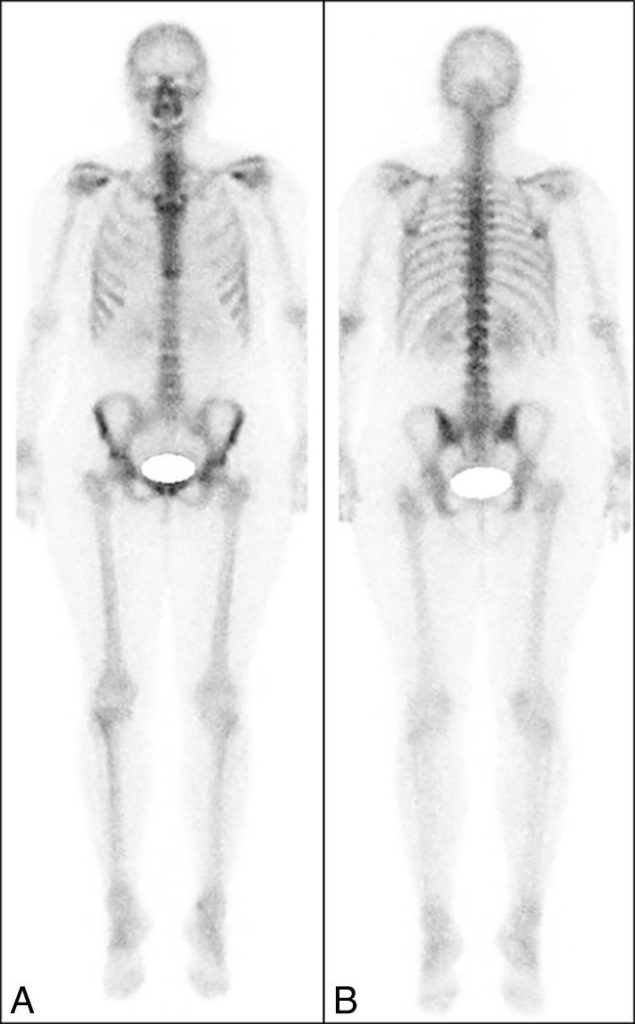

Fig. 132.3 Scintigraphie osseuse « corps entier » normale.

A. Balayage face antérieure. B. Balayage face postérieure.